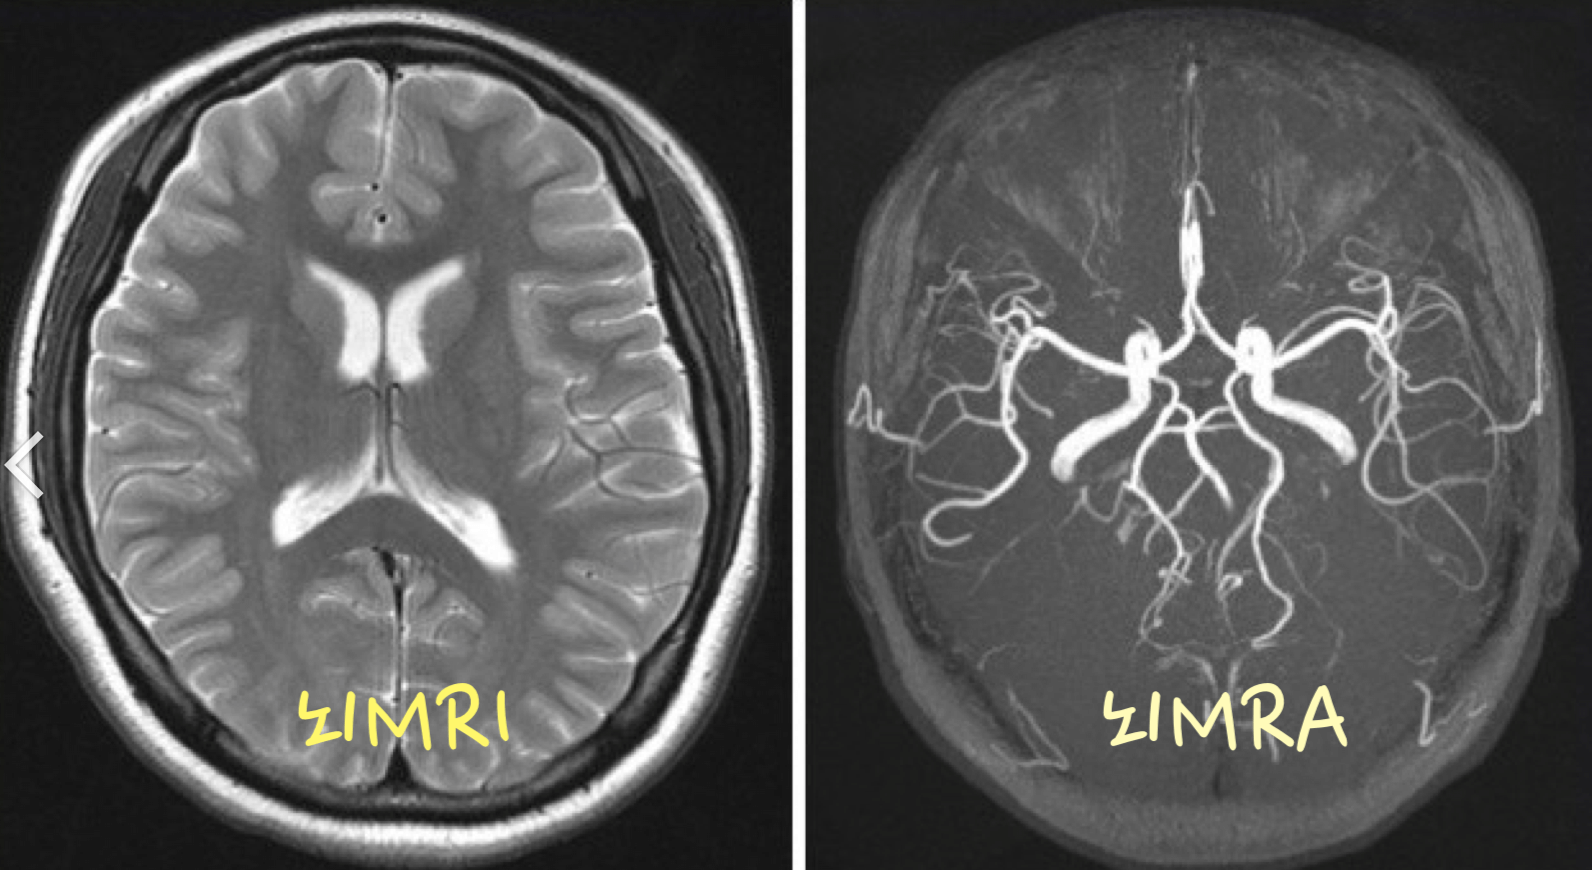

위 두가지 방법의 차이점은 사진을 한번보면 대략 어떤 차이가 있는지 한번에 알수 있습니다. 아래 사진을 보시고 어떤 차이가 있는 지 확인해 보세요.

▣ MRI MRA 사진

뇌MRI를 보시면 종양과 같은 것은 쉽게 찾을수 있을것 이고, 뇌MRA를 보시면 혈류를 볼수 있습니다. 즉 MRA는 혈관에 문제가 생긴것은 보다 쉽게 찾아낼수 있는 검사 입니다.